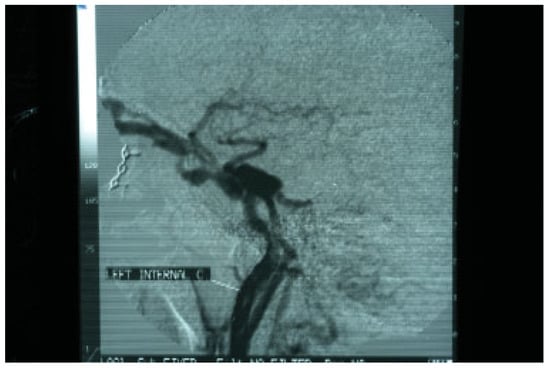

Two days after the removal of the foreign materials, there was a dramatic deterioration of the patient’s clinical presentation with intense ocular pain, worsening of exophthalmos, nausea, and vomiting. The patient also complained of “strange sounds in the cranium like water tapping.” Clinical examination revealed a systolic thrill on palpation of the left eye and a systolic wheeze on auscultation of the left frontal and temporal area. Measurement of intraocular pressure was subsequently performed and an intraocular pressure of 13 mm Hg in the right and 24 mm Hg in the left eye were recorded. Visual acuity was measured 5/6 vision and fundus examination revealed venous dilatation without further pathologic signs. The finding of intensive dilation of the left upper ophthalmic vein in the primary computed tomography was reevaluated and a posttraumatic CCF was suspected and included in the differential diagnosis. A new CT of the left orbit was ordered which revealed a threefold dilation of the cavernous sinus (Figure 4). The digital subtraction angiography (DSA) confirmed the diagnosis of CCF as it revealed a dilation of the cavernous sinus, a blood shunt between the lumen of the internal carotid artery and the cavity of the cavernous sinus, and a dilation of the upper ophthalmic vein (Figure 5).

The suspicion for the formation or rupture of a posttraumatic intracranial aneurysm of the intracavernous segment of the internal carotid artery is set by the clinical findings and is confirmed with further imaging assessment. The method of choice is four-vessel DSA, because it provides information on the location and size of the aneurysm or fistula [15,16]. Standard CT of the brain is usually performed at admission and may reveal signs of aneurysm or CCF formation such as ophthalmic vein dilation, basilar skull fractures, bony spicules, or herniation of the cavernous sinus into the sphenoid sinus [11].

Figure 5. Digital subtraction angiography (DSA) confirming the presence of a carotid cavernous fistula. A marked dilation of draining vessels can also be observed.